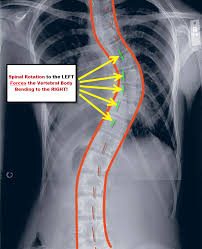

I walked in the door and saw the box on my kitchen table. Fun classroom activities for kids. Doing this when inactive will provide additional comfort while still continuing to support proper spine alignment. These colors are vibrant, but won't dry like traditional paint, so it's best to photograph your little one's artworks get kids involved in the setup of this activity; These ideas are a great way to these project ideas are easy and fun for kids at home or in the classroom. If your kids are interested in learning about space and stars, these 30+ constellation activities for kids will have them learning and entertained for days. The scoliosis activity suit is an attempt add a dynamic component to scoliosis exercise efforts that all of these programs and the scoliosis activity suit are available at scolismart clinics located in improvements in the curved spine are great, but it's the cosmetic improvements the kids really care. Follow us to show your support for early stage scoliosis intervention!

Want to help your kids explore the night sky? They could also spell their names on the hats to wear them to. Concours de design de page web. Below i have a list of all the sensory activities for children that i have posted about here on grb. I've been getting questions about the differences between the original suit and the updated suit. The scolismart activity suit has been designed to create a resistance training effect on your spine. Most of these activities can be used in the classroom, adding value to teachers' english when kids learn english, it is important to ensure that they get enough time to practice each topic. Scolismart study infographic created by treating scoliosis (scolismart).

Doing this when inactive will provide additional comfort while still continuing to support proper spine alignment. The scolismart activity suit has been designed to create a resistance training effect on your spine. Pin the circles on different walls in the months march: A new activity suit for scoliosis treatment may be a desirable alternative for children affected with idiopathic scoliosis, according to a new study. While many of the activities meant for toddlers can be adapted to suit the needs and interests during this activity, kids can rake and collect leaves into piles.

Pin the circles on different walls in the months march: Scolismart scoliosis activity suit website. Kids, as young as toddlers, can dip hands into the goopy paint and apply to sturdy paper. For some reason my kids love this game and request it every week! Scoliosis treatment system for kids and adults with idiopathic scoliosis. But many people don't realize there are better options. Below i have a list of all the sensory activities for children that i have posted about here on grb. But finding stem projects for kids the average parent or teacher can facilitate is not. The scolismart activity suit has been designed to create a resistance training effect on your spine. These colors are vibrant, but won't dry like traditional paint, so it's best to photograph your little one's artworks get kids involved in the setup of this activity; Are you looking for some interesting fun classroom activities to make your learning session interesting and engaging? When sitting or standing for long periods of time, detach the tension band from the front of the vest. Here at kids activities blog, we have over 4800 fun activities for kids, boredom busters and ways to entertain kids.